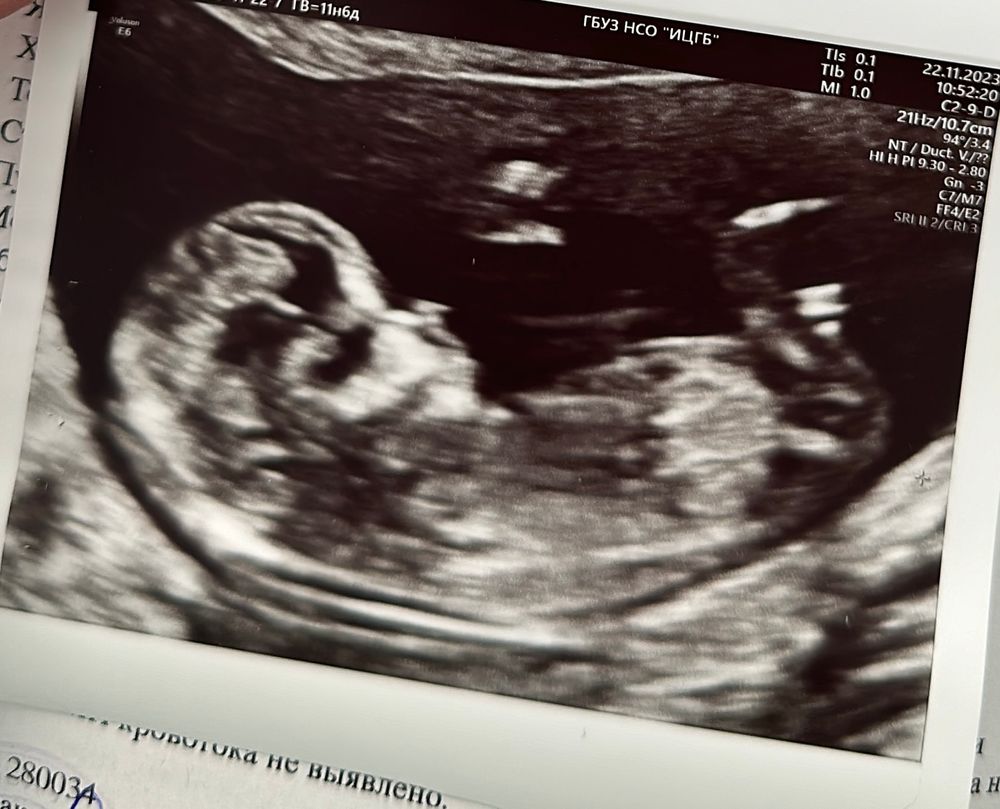

Скрининг 12 недель

Мальчик скорее всего☺️

Ого, какой малыш большой на 12 недели уже 🤗Дай Бог здоровый пусть будет малыш. Я надеюсь и у меня так же хорошо будет видно на первом скрининге малыша ☺

Я вижу девочку, у меня половой бугорок был к верху

Девченка))) думаю по бугорку

Добрый вечер! Парень?)

Сколько сердцебиение у малыша ?

Галина Куканова, 165)